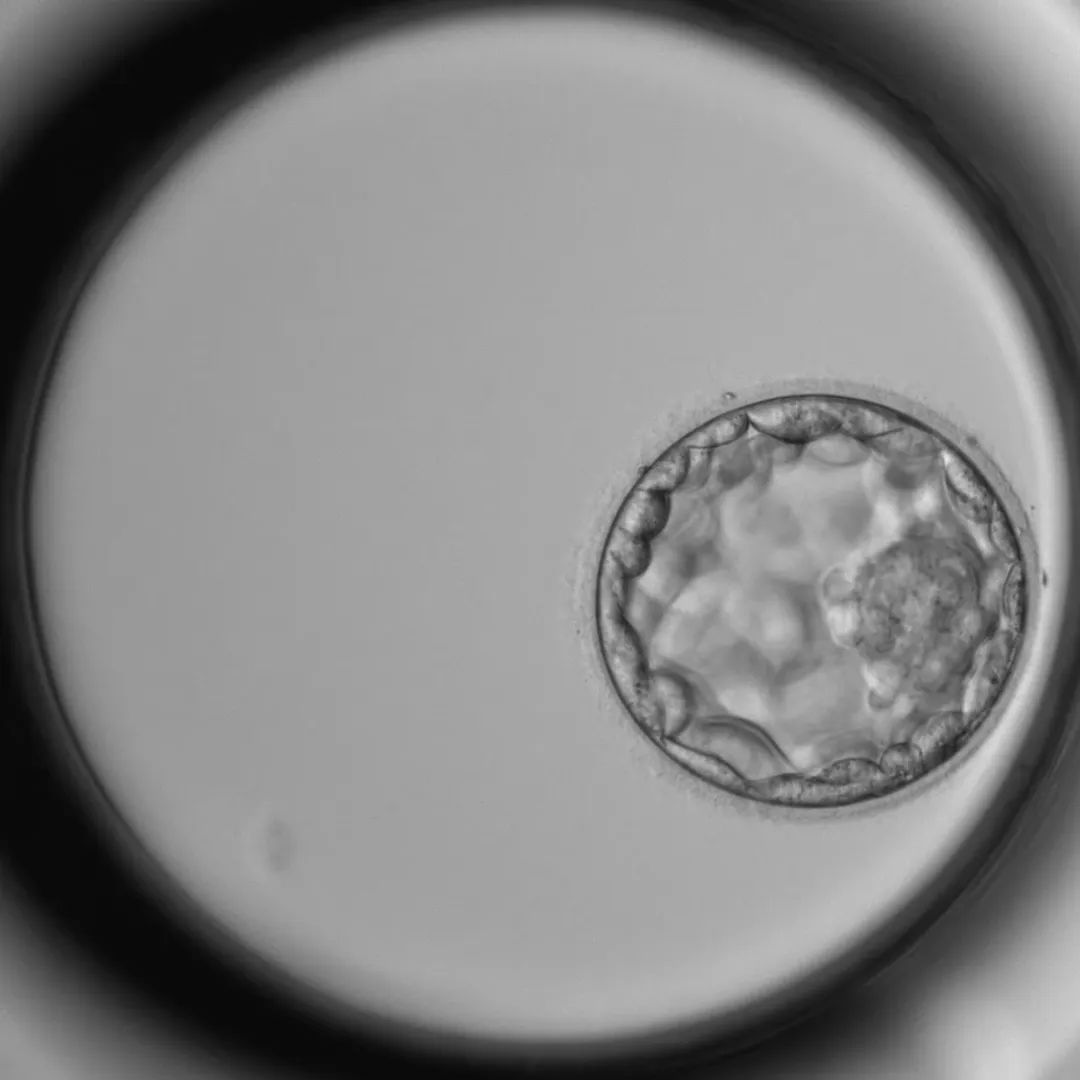

看着已经在培养箱中孕育的胚胎,高博士知道,等待它们的最终考验就在不远处——在生殖实验室里有一套完整的评分系统,这套评分系统,严苛地将胚胎分为多个等级,决定着它们能否获得“子宫入场券”。

很快,一个各方面都表现得相当优秀的胚胎,被高博士一眼相中,等待着被移植的命运。

这里不仅模拟着胚胎最熟悉的“母体”环境,还能实时监测胚胎们自由发育的情况——按照这种势头,那些被挑中的优质胚胎,将会被标记为“明日之星”,要不了多久,就有机会回归母亲的怀抱。

当高博士看到优质胚胎时,心情会舒畅一整天!